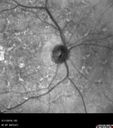

62 year old man does not notice much vision. He has no history of vision loss in either eye. He has family members with glasses but does not know of any eye problems in the family. VA OD: Dcc20/20-1 PH20/16 NccJ3 VA OS: Dcc20/40 PH20/25 NccJ5

Stargardt's Macular Dystrophy691 views62 year old man with good vision00000